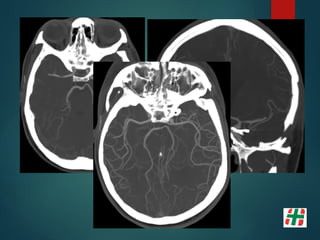

STROKE ISQUÉMICO AGUDO

Isquemia Cerebral

 Alteración en el aporte de oxígeno y nutrientes al

parénquima encefálico.

 80% de los Stroke en general.

 3er causa de muerte general.

 1er causa de morbilidad.